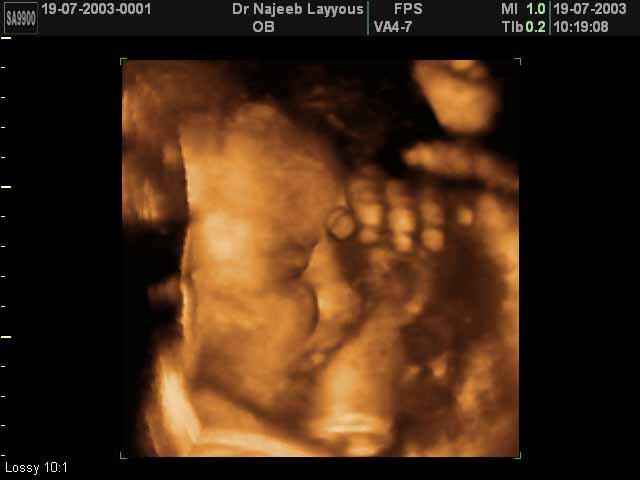

صور جانبية لرأس الجنين بجهاز الالتراساوند ثلاثي الأبعاد | الدكتور نجيب ليوس